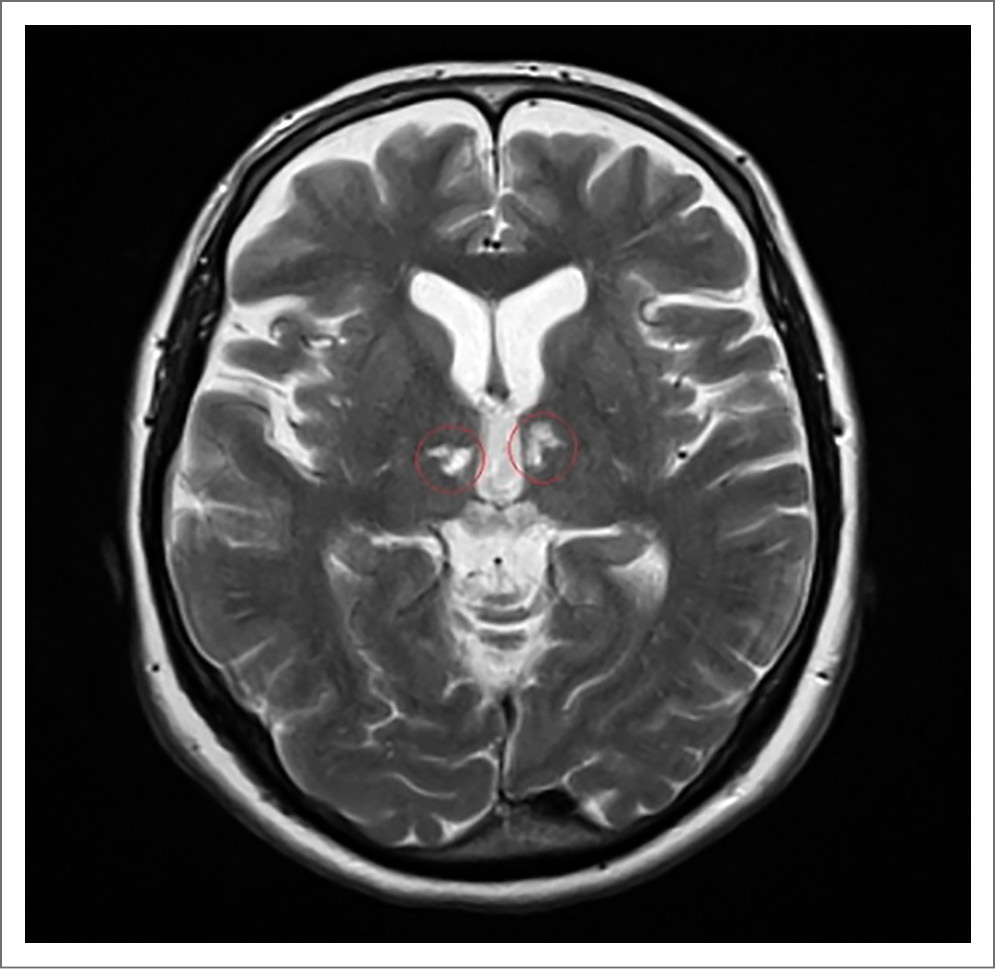

Состояние больной через 1 ч после поступления в стационар ухудшилось, в течение нескольких минут наросла общемозговая симптоматика до комы. На экстренной магнитно-резонансной томографии (МРТ) ГМ, выполненной по программе head general SE, TSE, TOF, TIRM c толщиной срезов 1, 4, 5 мм в аксиальной, сагиттальной и фронтальной проекциях с 3D-реконструкцией виллизиева круга без внутривенного контрастного усиления, обнаружены очаги острейшей ишемии в области таламусов с обеих сторон в бассейне таламоперфорирующих артерий размерами 1,0×1,2 см справа и 1,1×0,9 см слева. На времяпролетной МР-ангиографии виллизиева круга МР-сигнал от обеих задних мозговых артерий в сегменте P1 ослаблен. Признаки сосудистой мальформации и аневризмы сосудов ГМ не определены. Заключение МРТ-исследования: очаги острейшей ишемии в области таламусов с обеих сторон, стеноз обеих задних мозговых артерий в сегменте P1 (возможно, гипоплазия); рис. 1–3.

Рис. 3. Пациентка С., 72 года. МРТ-исследование ГМ 20.02.2020: на измеряемой карте диффузии (ADC) в аксиальной проекции наблюдается ограничение диффузии найденных очагов.